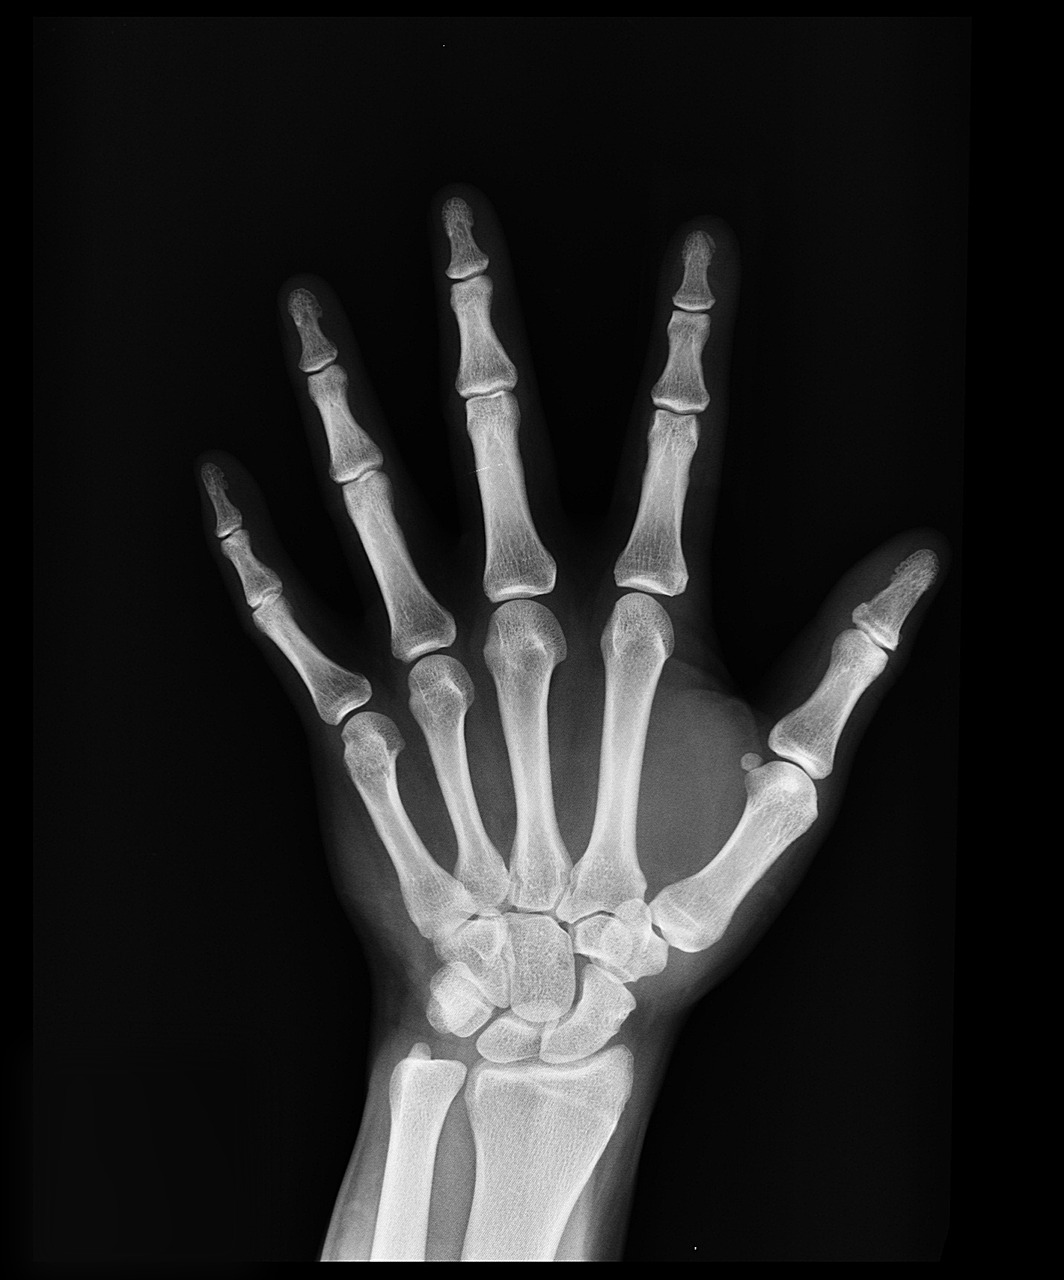

골다공증은 뼈가 약해지고 쉽게 부러지는 질환으로, 특히 여성에게 더 많이 나타납니다.

칼슘과 비타민 D는 뼈 건강의 핵심입니다. 뼈는 지속적으로 생성되고 소실되기 때문에, 영양소 섭취가 부족하면 골밀도가 점점 낮아질 수 있습니다.